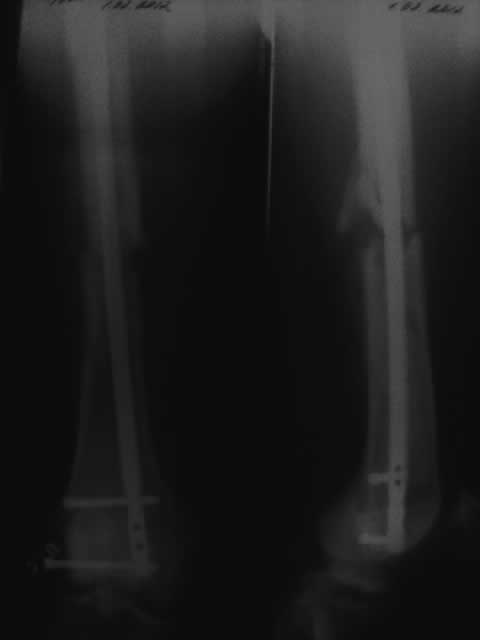

Мне 38 лет вес 74кг прошло 3 месяца после операции добавляю последний снимок от 1го февраля посмотрите пожалуйста.